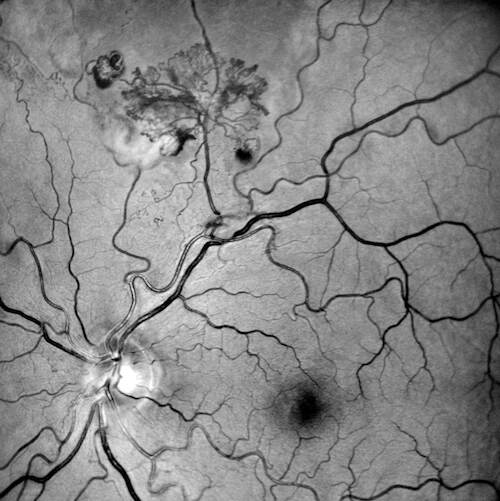

Fluorangiografia (FAG)

L’esame fluorangiografico ha confermato la natura ischemico-proliferativa del quadro:

- Fasi precoci: Rapida iperfluorescenza del complesso vascolare frondiforme.

- Fasi tardive: Marcato e progressivo leakage di colorante (staining e diffusione nei tessuti circostanti), inequivocabile segno di neovascolarizzazione retinica attiva.

- Ischemia: È ben delimitabile una vasta area di alterata/ridotta perfusione capillare retinica nel settore superiore, che funge da substrato ischemico primario per la proliferazione.

- Analisi degli shunt/collaterali: Gli shunt/collaterali vascolari apprezzati alla retinografia si confermano come vasi ad iperfluorescenza tardiva relativamente contenuta rispetto al complesso neovascolare principale, con pattern angiografico compatibile con canali vascolari di remodelling piuttosto che con neovasi attivi con leakage intenso. Questo pattern è in accordo con la letteratura che distingue i collaterali — caratterizzati da iperfluorescenza stabile senza leakage marcato — dai neovasi — caratterizzati da leakage progressivo nelle fasi tardive3.

È essenziale notare l’assenza di staining diffuso della parete vascolare o di segni di perivasculitis (come il fern-like leakage), che rende altamente improbabile l’ipotesi di una vasculite retinica in fase attiva. Allo stesso modo, non si rilevano dilatazioni sacciformi o fusiformi tipiche del macroaneurisma arterioso, escludendolo come lesione patogenetica primaria.

| FAG | Area di non-perfusione superiore. Leakage tardivo marcato dal ciuffo neovascolare. Iperfluorescenza contenuta degli shunt. Assenza di staining vasale diffuso. | Ischemia retinica settoriale con NVE (neovascolarizzazione altrove) attiva. Esclusione di vasculite diffusa e macroaneurisma. |